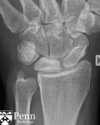

Fratura de Chaffeur

Fratura do processo estilóide do rádio.